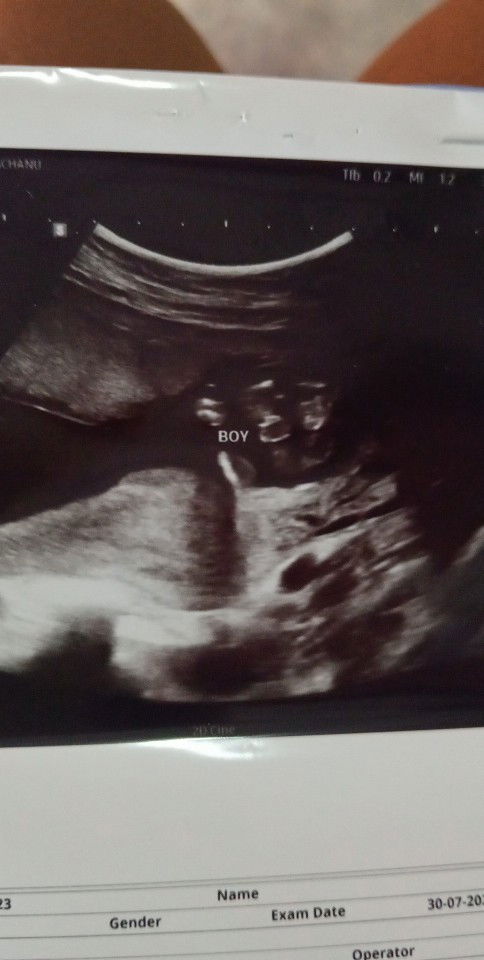

เพศลูกหญิงหรือชาย

แม่ว่าชัวยังค่ะ กลัวกลับไปเป็นหญิง ตอนท้องโต ซาวตอน 16week#ขอบคุณล่วงหน้าสำหรับความคิดเห็นค่ะ